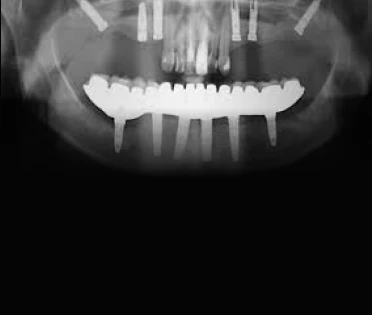

All-on-4 Standard:

Casos ideais com anatomia favorável